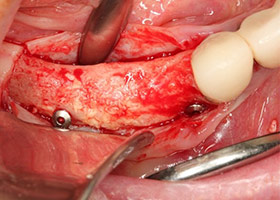

4.移除牙橋與殘根,牙脊明顯萎縮。

5.牙脊萎縮處進行補骨手術。

6.完成補骨手術。